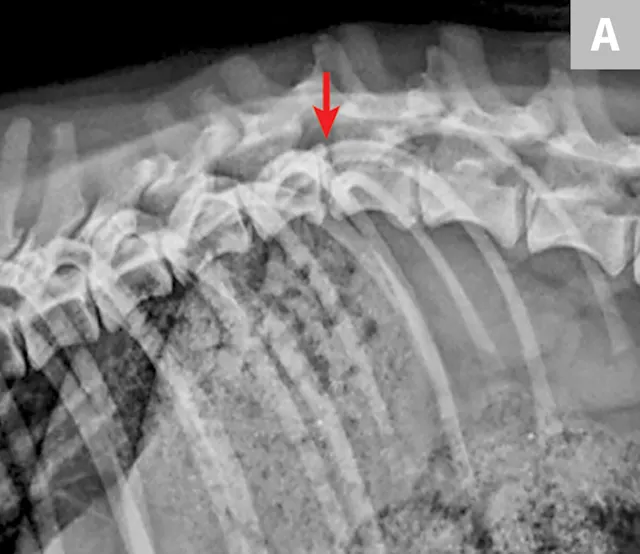

Survey radiographs of the vertebral column should be obtained, as well as chest and abdominal radiographs to assess for concurrent injuries. Horizontal beam radiographs are strongly preferred for obtaining ventrodorsal views of the vertebral column, as they do not require the patient to be moved out of lateral recumbency, which could further compromise the integrity of the vertebral column. Although sufficient for diagnosing significantly displaced vertebral fractures and luxations, radiographs are not adequate for predicting the degree of spinal cord injury or assessing the degree of vertebral instability (Figure 1 and Figure 2).

Figure 1

Lateral radiograph of a dog following unknown trauma. There is a complete oblique fracture (arrow) of the L6 vertebral body and luxation of the L6-L7 articular processes, with severe cranioventral displacement of the caudal segment. Despite the degree of displacement, this patient retained voluntary movement in both pelvic limbs on initial examination and made a functional recovery following reduction and stabilization of the fracture/luxation and 8 weeks of crate confinement.